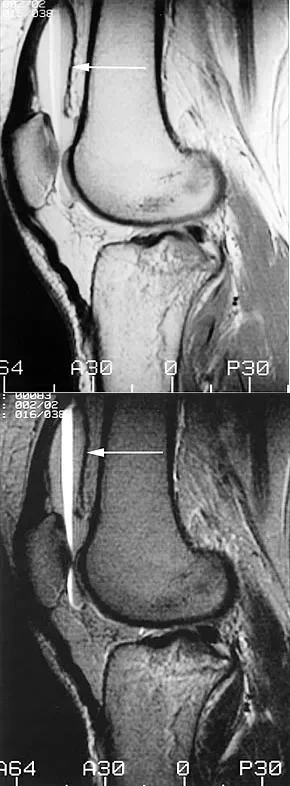

The MRI scans shown demonstrate a lipohemarthrosis in the knee. Which of the following is the most common underlying etiology for this specific MRI finding?

Explanation

Correct Answer: C

Lipohemarthrosis is characterized by the layering of fat and blood within a joint cavity. The most common cause is an intra-articular fracture, which allows marrow fat to escape into the joint space. On MRI, it typically shows a superior layer of fat, a central layer of serum, and an inferior layer of red blood cells. While an ACL tear causes a hemarthrosis, it does not typically cause a lipohemarthrosis unless accompanied by an osteochondral fracture.

A patient presents to the emergency department with acute knee swelling following a high-energy trauma. T1-weighted MRI is obtained and shown. The distinct layering effect seen in the suprapatellar pouch is most strongly associated with which of the following underlying injuries?

Correct Answer: Intra-articular fracture

The MRI scan demonstrates a lipohemarthrosis, characterized by the layering of fat, serum, and red blood cells in the joint space. The superior layer contains fat (high signal intensity on T1), the middle layer contains serum, and the dependent layer contains red blood cells. The presence of a lipohemarthrosis is highly indicative of an intra-articular fracture, which allows marrow fat to escape into the joint cavity. While ligamentous and meniscal injuries can cause a hemarthrosis, they do not typically introduce marrow fat into the joint unless accompanied by an osteochondral defect or fracture.

A patient presents with acute knee swelling following trauma. MRI scans (T1 and T2-weighted) are shown. The layering effect seen within the joint space is most strongly associated with which of the following underlying injuries?

The MRI shows lipohemarthrosis, characterized by layering of fat (superior, high signal on T1), serum (central, low signal), and red blood cells (inferior, low signal). This finding is highly indicative of an intra-articular fracture, which allows marrow fat to escape into the joint space.

A patient presents with acute knee swelling following trauma. T1- and T2-weighted MRI scans are shown, demonstrating a characteristic layering effect within the joint effusion. This finding is most strongly associated with which of the following underlying injuries?

The MRI scans demonstrate a lipohemarthrosis, characterized by the layering of fat (superiorly, high signal on T1), serum (centrally), and red blood cells (inferiorly, low signal). The most common cause of a lipohemarthrosis is an intra-articular fracture, which allows marrow fat to escape into the joint space. While an ACL tear can cause a hemarthrosis, it typically does not produce a lipohemarthrosis unless accompanied by an osteochondral fracture.